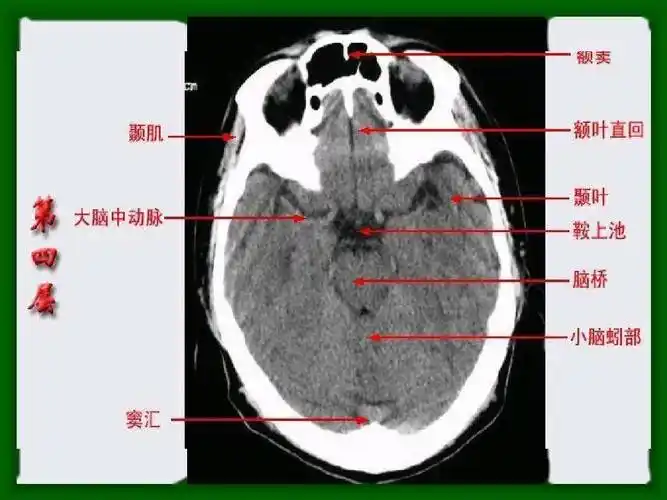

头颅ct 解剖图谱,人手一份

影像医生必须掌握的头颅ct解剖与常见出血梗死判读

头颅ct解剖与常见出血梗死判读